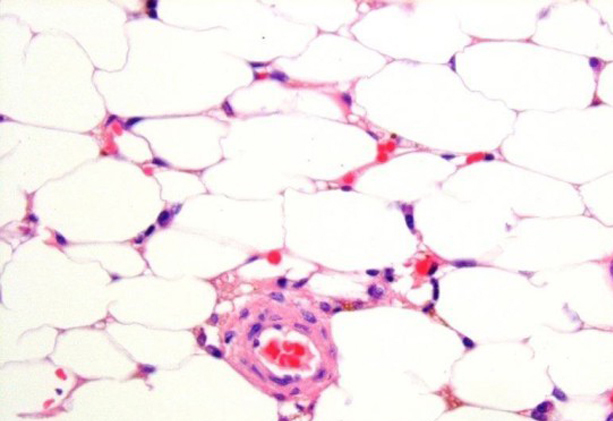

aplastic anemia

Scientists searching for treatments for severe aplastic anemia

NIH researchers want to work with patients with severe aplastic anemia to explore new treatments and medications.